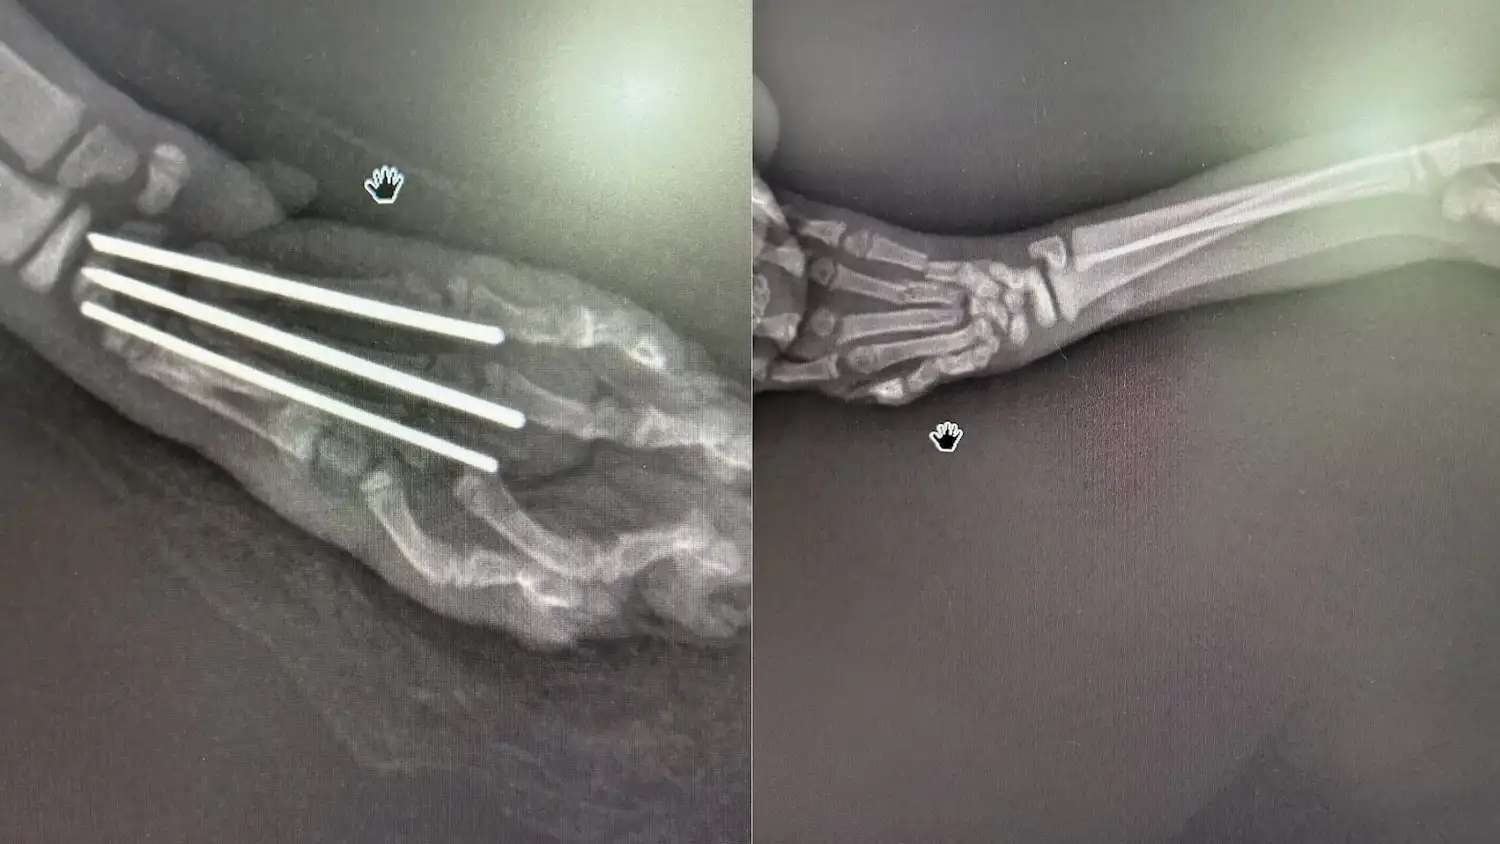

Kemik kırıkları, iç organ anomalileri ve solunum yolu problemlerinin tespitinde görüntüleme, tanı sürecinin temel taşıdır. Vetra Veteriner Kliniği olarak Ataköy’de sunduğumuz dijital röntgen hizmetiyle, evcil hayvanınızın iç yapısını yüksek çözünürlüklü görüntülerle saniyeler içinde değerlendiriyor; tedavi planını vakit kaybetmeden oluşturuyoruz.

Dijital röntgen; kemik ve iskelet sistemi sorunlarından iç organ değerlendirmesine geniş bir tanı yelpazesi sunar. Kliniğimizde sıklıkla başvurulan durumlar şunlardır:

• Kırık, çatlak ve eklem kayması

Geleneksel röntgende film banyosu ve uzun bekleme süreci söz konusuyken, dijital sistemlerde görüntü anında ekranda değerlendirilir. Radyasyon dozu belirgin biçimde daha düşüktür; bu da özellikle tekrarlı çekim gerektiren kronik hastalık takiplerinde önemli bir avantaj sağlar. Görüntüler dijital ortamda saklanır ve gerektiğinde uzman görüşüne kolaylıkla iletilebilir.